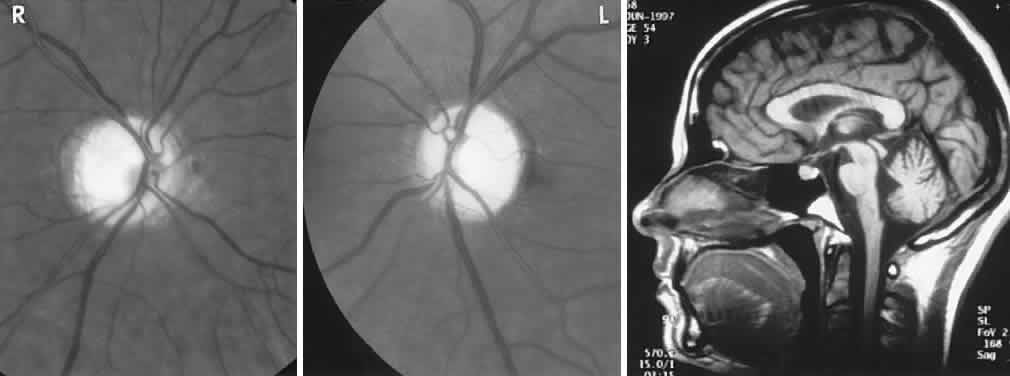

As noted, surprising numbers of etiologically diverse diseases simultaneously or sequentially involve the retina, uvea, and brain. Of these, the Vogt-Koyanagi-Harada syndrome is best known, characterized by bilateral diffuse granulomatous panuveitis, whitening (poliosis) especially of eyebrows and lashes, skin depigmentation (vitiligo), alopecia, meningismus with headache and CSF pleocytosis, rarely focal CNS signs, tinnitus, hearing loss, and vertigo. Autoimmune inflammation directed against melanocytes seems the basic mechanism, with an epidemiologic predilection for pigmented racial groups, especially in Japan and other parts of Asia; it is uncommon in whites. Prolonged corticosteroid and other immunosuppressive therapy is effective.120

Zonal outer retinopathies (AZOOR, see above) can show choroidal changes and are reported with CSF pleocytosis, cervical myelopathy, and periventricular white matter lesions on MRI, abnormal ERG, perivenous sheathing, and retinal pigment migration.121 Posterior placoid pigment epitheliopathy (APMPPE, see above) also is reported to occur in association with headaches, CSF aseptic cellular reaction, TIAs, inner ear symptoms, and multiple strokes, requiring immunosuppressive agents for presumed cerebral vasculitis.122 The classification found in Table 5 highlights the difficult diagnostic dilemma posed by these diverse disorders.